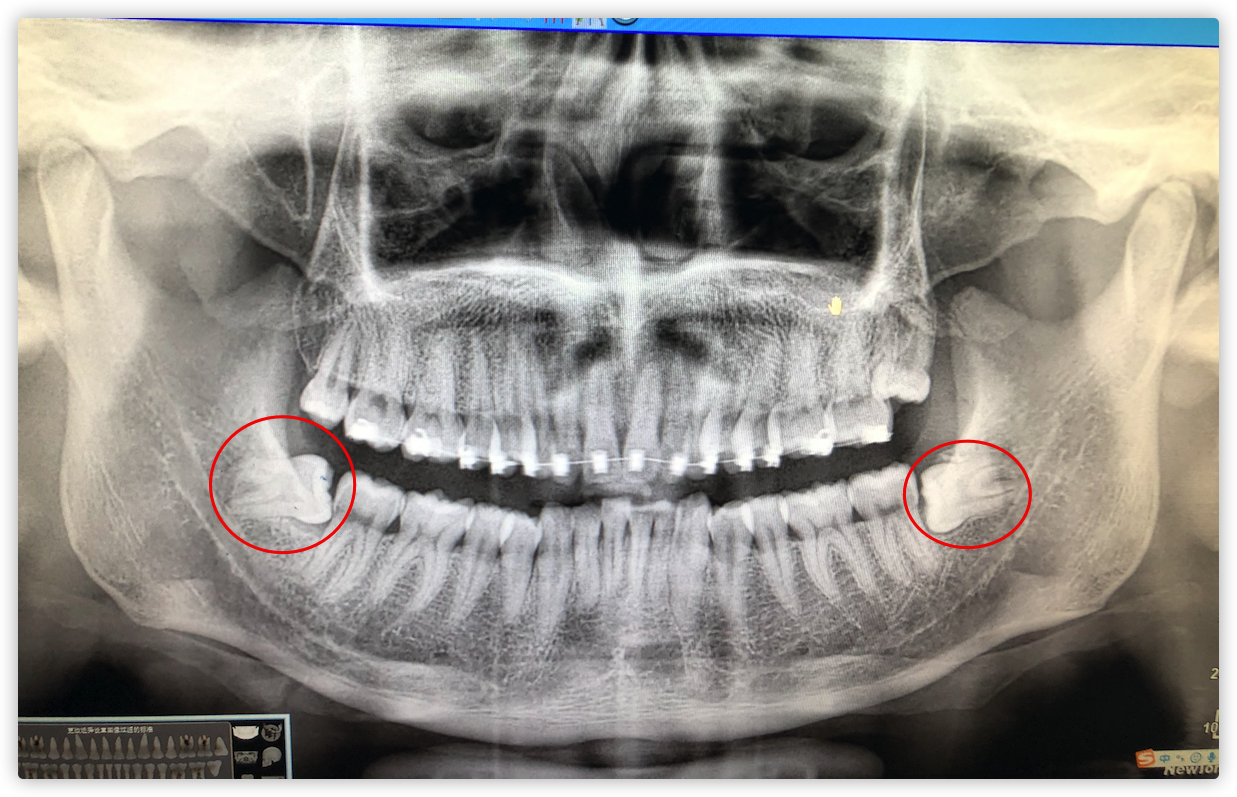

像我自己的话,经过医生的判断,最终需要拔掉了四颗智齿,上下左右各两颗,分了两次拔,一次两颗,拔牙那滋味,我依然清楚记得拔完牙齿后,我整个背都被汗水浸湿了,拔牙麻药消了后,真是生不如死,感觉咽口水都痛,第二天起来,脸都是肿的,总之矫正牙齿,就得做好拔牙的心里准备。

放一张当时拔牙时留下的照片: